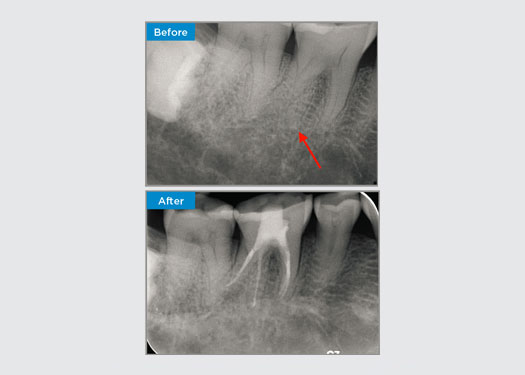

Il paziente si presenta con una pulpite irreversibile al dente 46. Dalla radiografia preoperatoria, il dente 46 si presenta con una radice distale aggiuntiva (morfologia dei denti Radix Entromolaris). Una scansione CBCT ha confermato la presenza di radice DL con grave curvatura della radice. Un'attenta selezione degli strumenti è fondamentale per questa delicata radice DB.

Dott. Jack Lin, Endodontista, Sidney, NSW Australia